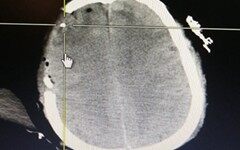

脑积水治疗设备的突破创新,帮助CereVasc斩获4390万美元A轮融资【海外案例】

CereVasc获得由Perceptive Xontogeny Venture和ATON Partners领投的4390万美元A轮融资,该轮…